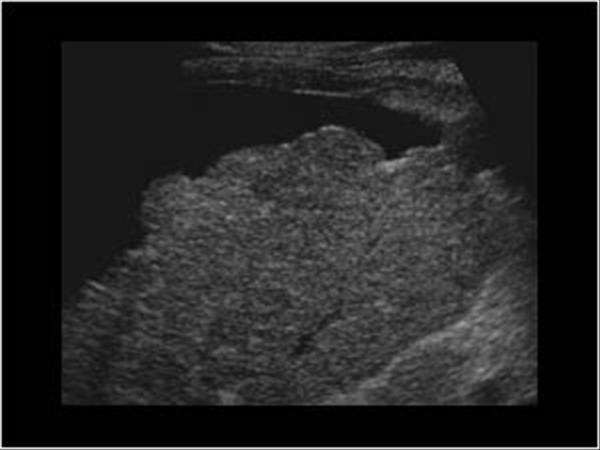

What is Cirrhosis?

A chronic degenerative disease in which there is parenchymal necrosis, regeneration and fibrous tissue resulting in disorganization of lobular architecture. Lobules are infiltrated with fat. Commonly caused by alcoholism.

What is the sonographic appearance of Cirrhosis?

Hepatomegaly

Increased echogenicity and attenuation

Size

decrease of right lobe

Size increase of left and caudate

lobe

Nodularity

Fibrosis

Hepatospenomegaly

Ascites

Portal

hypertension

Hepatoma tumors

caudate lobe may be spared